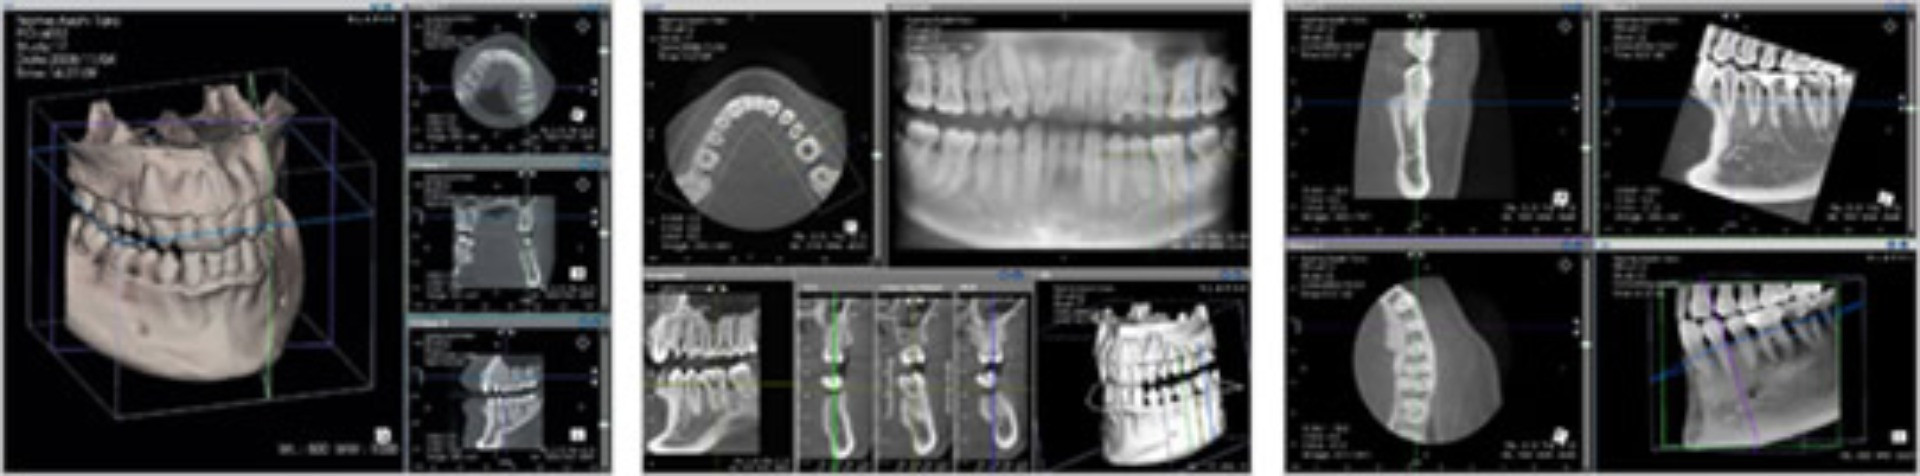

阿部歯科導入の歯科用CT「AUGE(オージェ)SOLIO」は、歯科用レントゲンにおいて、早くからCTの開発研究に取り組み、今までにも高精細画質な歯科CT装置を開発している(株)朝日レントゲン工業の最新鋭CTです。

阿部歯科導入の歯科用CT「AUGE(オージェ)SOLIO」は、歯科用レントゲンにおいて、早くからCTの開発研究に取り組み、今までにも高精細画質な歯科CT装置を開発している(株)朝日レントゲン工業の最新鋭CTです。

今までのエックス線画像では、写真のような平面での診断しかできませんでしたが、CTでは、三次元の立体画像で診断ができるため、今まで見えなかった部分が容易に確認でき、従来のレントゲン撮影法よりも、正確で精密な診断が可能になりました。

CTは、歯だけでなく、顎の内部構造や上顎洞の形態、粘膜の状態、病巣などを立体画像で確認できるので、今までわかりにくかったところも見落とすことなく、診断・治療することが可能です。

CTは、歯だけでなく、顎の内部構造や上顎洞の形態、粘膜の状態、病巣などを立体画像で確認できるので、今までわかりにくかったところも見落とすことなく、診断・治療することが可能です。